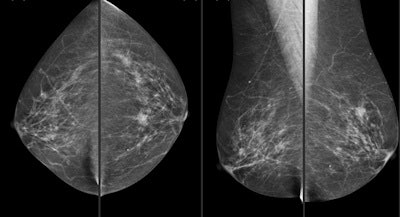

The prospective study included data from 21,321 consecutive screening mammograms (Senographe 2000D, GE Healthcare) in incident rounds (2010-2012). Exams were interpreted in a protocol that included single reading plus CAD (SecondLook, Premier, iCAD). These studies were then compared with data from 47,462 consecutive screening mammograms in incident rounds (2004-2010) that were interpreted following a protocol with double reading plus arbitration.